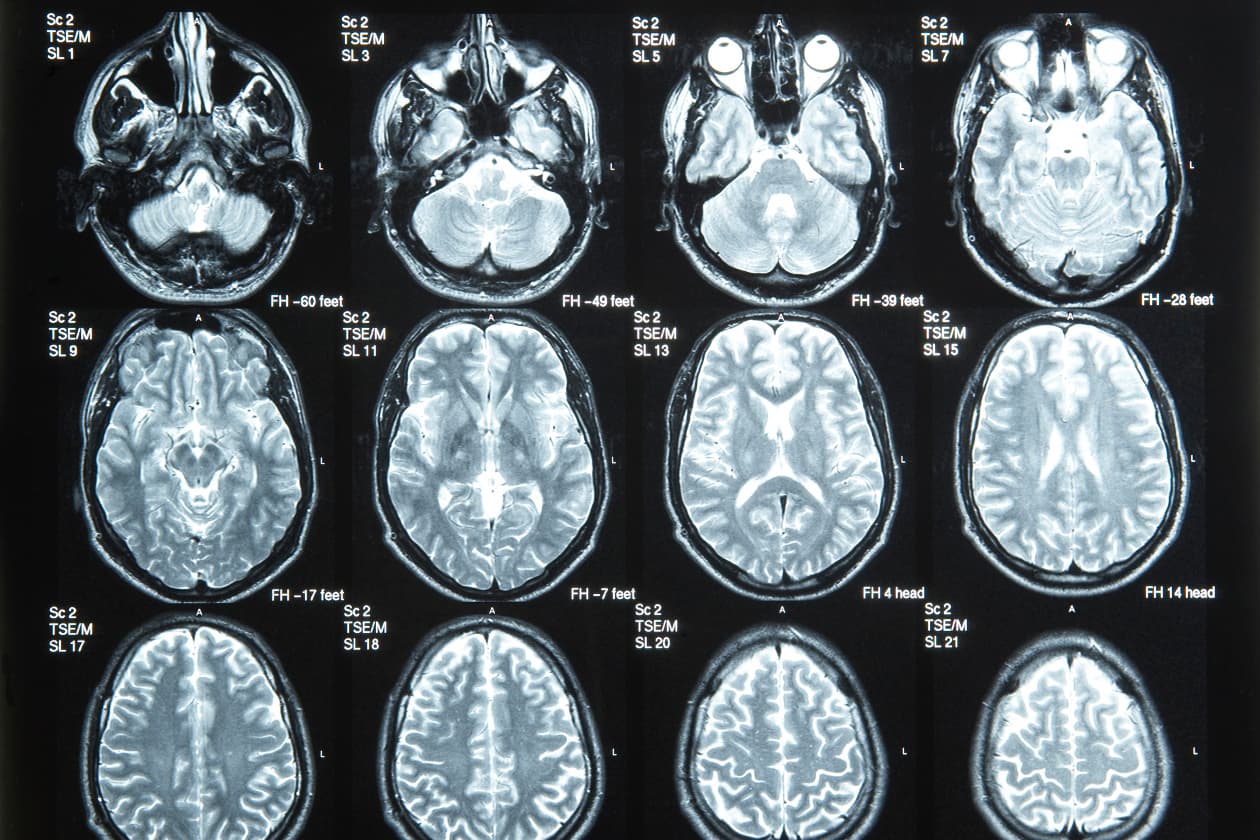

Algunos procedimientos con rayos X pueden ser evitados y sustituidos por una ecografía o una resonancia magnética. Las ecografías son útiles en exámenes de pelvis y abdomen, testículos y durante el embarazo. La resonancia magnética se utiliza principalmente para la cabeza, la columna vertebral y las articulaciones.